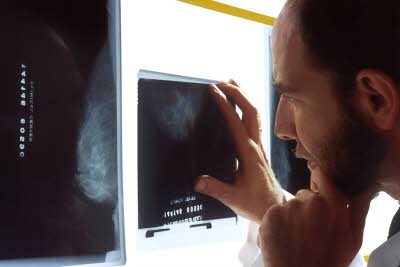

흉부X선 검사 실시 후 결핵의심자에 한하여 확진검사 실시합니다.